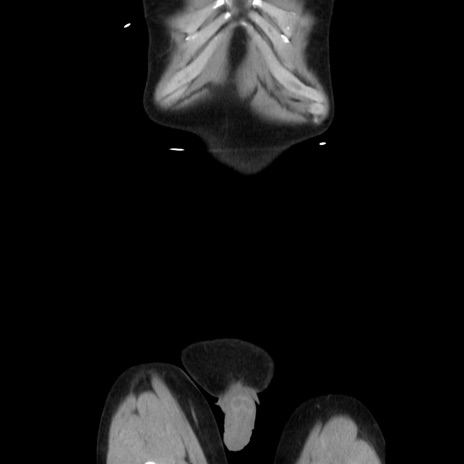

症例37(冠状断像)

症例

【症例】40歳代 男性

【主訴】腹痛

【現病歴】4時間ほど前に電車に乗車中に臍部上より腹痛出現。徐々に増悪し起立困難となり、救急外来受診。生ものは数日食べていない。今朝お雑煮を食べた。

【既往歴】なし

【身体所見】BT 36.8℃、BP 117/84mmHg、HR 91/min、SpO2 97%、苦悶様、腹部:臍上部広範囲圧痛あり、反跳痛±

【データ】WBC 8100、CRP 0.03